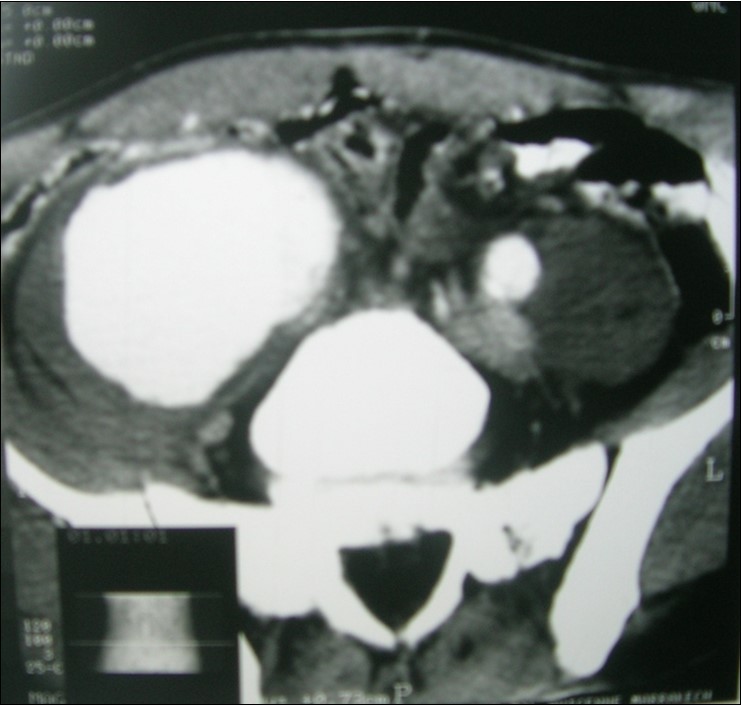

A45-year-old man, with no prior pathologic antecedent was admitted to the internal medicine department for a 3weeks history of abdominal pain. This symptom occurred in the context of apyrexia and 4 kilogram weight loss. Abdominal examination was a painful abdomen, distended. The skin examination noted painful genital andoral ulcers with pustlar lesions in the back. Angio CT scan revealed an aneurysm of the right common iliac artery (Figure 1).Artégraphie the lesion showed the same described above, showing the saccular aneurysm (Figure 2). He had no other aneurysmal localizations.

Figure 1.Angio CT scan revealed an aneurysm of the right common iliac artery.